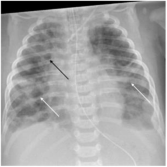

Рисунок 2. Рентгенограмма ребенка с бронхолегочной дисплазией. Ранние признаки: небольшое прикорневое помутнение и мелкая зернистость; поздние признаки: грубые сетчатые помутнения (белая стрелка), кистозные просветления (черная стрелка), ателектаз и гиперинфляция легких